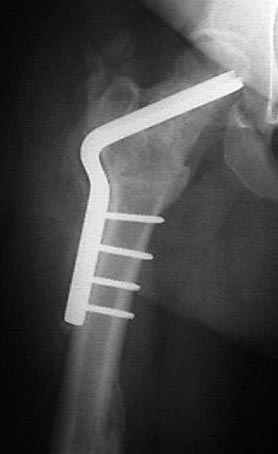

На рисунке N1 предоперационный план лечения ложного сустава шейки бедра- линия ложного сустава, угол и направление введения импланта, клиновидная остеотомия в градусах и миллиметрах, второй снимок после коррекции, расчет, на сколько удлиняется конечность и размеры импланта;

N3 рисунок окончательный снимок, после операции моя рентгенограмма должен выглядеть примерно как эта картина. На N4 снимке клин перед удалением; N5 послеоперации 3 нед.; N6 окончательная рентгенограмма.

(доложен в Ст. Петербурге 2003 и в Москве 2004)

варус при проксимальном отделе 95 градусной пластиной.